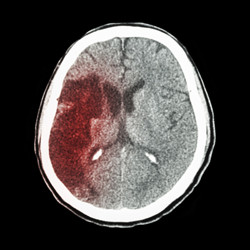

Udar jest chorobą naczyń mózgowych, w której przepływ krwi do mózgu jest zaburzony powodując śmierć jego komórek. Prowadzi to do szeregu wyniszczających objawów, takich jak niedowład, utrata pamięci a nawet zgon.

Europejskie badania nad udarem otrzymały znaczące wsparcie dzięki utworzeniu interdyscyplinarnej sieci badawczej "European stroke research network" (EUSTROKE)(odnośnik otworzy się w nowym oknie) . Uczelnie, rządy, przemysł, sektor non profit i stowarzyszenia pacjentów połączyły siły, tworząc tę wspólną inicjatywę. Działania sieci European Stroke Network (ESN) obejmują szereg obszarów, w tym biologię naczyń mózgowych, zapobieganie udarom i obrazowanie. Członkowie projektu przeprowadzili badania kliniczne i przedkliniczne, dzielili się wynikami, organizowali szkolenia i rozwijali platformy badawcze. Naukowcy koncentrowali się na wyjaśnieniu zmian, jakie zachodzą w barierze krew–mózg i w jednostce nerwowo-naczyniowej na skutek udaru i obrzęku mózgu. Jednostki nerwowo-naczyniowe składają się z szeregu komponentów komórkowych i niebędących komórkami. Należą do nich mózgowe komórki nabłonkowe, astrocyty, komórki układu odpornościowego, blaszka podstawna naczyń krwionośnych i neurony, które łącznie wpływają na przenikalność bariery krew–mózg. Do celów eksperymentalnych uzyskano nowe lub zoptymalizowano i zwalidowano już istniejące mysie i ludzkie modele jednostki nerwowo-naczyniowej i bariery krew–mózg do badań in vitro. Opracowano też nowe protokoły obrazowania metodą rezonansu magnetycznego (RM), aby diagnozować udar i oceniać odzyskiwanie zdrowia po jego przejściu na poziomie molekularnym i jednostki nerwowo-naczyniowej. Korzystając z RM określano przenikalność bariery krew–mózg. Pomogło to w ocenie obecnie stosowanych i dopiero tworzonych leków, jak również strategii profilaktyki udaru, w tym stosowania neuronalnych komórek macierzystych i sonotrombolizy. Naukowcy oceniali też wpływ diety, ćwiczeń fizycznych, starzenia się, komórek progenitorowych, komórek układu odpornościowego i czynników obniżających poziom lipidów we krwi na jednostkę nerwowo-naczyniową i barierę krew–mózg. Przełomowym odkryciem było stwierdzenie, że w tkance mózgowej po udarze nie występują granulocyty (PMN). Innym kluczowym odkryciem był przełącznik warunkujący śmierć lub przeżycie komórki (PEA15/HKII), będący celem potencjalnych leków. Sieć badania ESN obejmuje ponad 1 350 ośrodków leczenia udaru na świecie, co ułatwia prowadzenie badań klinicznych nad tą chorobą. Konsorcjum nawiązało również współpracę transatlantycką z Canadian Stroke Network, aby usprawnić międzynarodowe badania. Ogółem prace projektu ESN są przełomowe pod względem wyjaśnienia patofizjologii udaru i opracowania innowacyjnych strategii diagnostycznych i terapeutycznych. Szeroko zakrojona współpraca międzynarodowa pomiędzy uczelniami, przedstawicielami przemysłu i kluczowymi stronami zainteresowanymi powinna przyczynić się do szybkiego wprowadzenia na rynek skutecznych produktów diagnostycznych i terapeutycznych do zastosowań klinicznych.